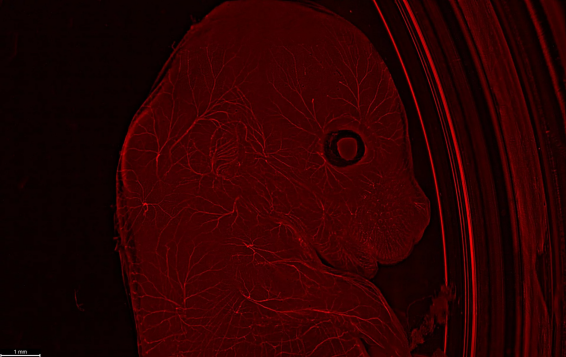

所介紹的工作流程以 Mateo TL 開始,它可以輕松直觀對類器官細胞培養(yǎng)進行觀察檢查。然后使用THUNDER成像儀對樣本進行成像,實時清晰觀察完整樣本深處的細節(jié),且不會失焦模糊。這項技術(shù)考慮了所有相關(guān)的光學(xué)參數(shù),確保獲得無霧的結(jié)果。THUNDER成像儀在研究 3D 細胞培養(yǎng)方面表現(xiàn)出色,能夠以增強的清晰度捕捉靜態(tài)和動態(tài)細胞狀態(tài)。

在 3D 細胞培養(yǎng)的研究中,端到端的工作流程展示了THUNDER成像儀在自動化檢測方面的dute能力,以高效研究下一代疾病模型。該系統(tǒng)允許以高速度和高靈敏度成像大樣本體積,如類器官——確保低光毒性和光漂白——在最佳條件下實現(xiàn)更高的通量。自動化最小化了用戶的干預(yù),即使在復(fù)雜實驗中也是如此。

清晰的THUNDER圖像,毫無模糊和霧靄,可以清晰地標(biāo)記信號和背景。這這就是使用 Aivia AI 圖像分析軟件進行基于人工智能的對象檢測、分割和分析的wanmei起點。通過量化生長速率、細胞遷移路徑和速度以及 3D 環(huán)境中的細胞相互作用等參數(shù),您可以深入了解您的 3D 培養(yǎng)物。